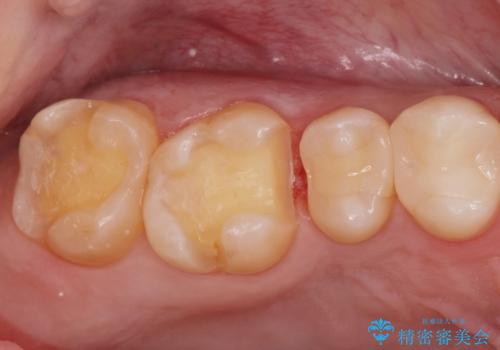

- 銀の詰め物をやりかえたいとの事で来院。

詰め物を外し、虫歯がない事を確認してからe-maxインレーで治療しました。

白く、適合の良い詰め物が入りました。セラミックは汚れや細菌付着しにくいので虫歯の再発のリスクが低くなります。